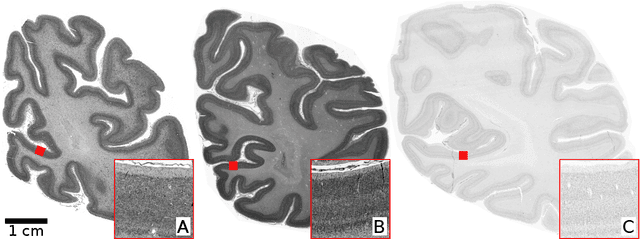

Abstract:Human brain atlases provide spatial reference systems for data characterizing brain organization at different levels, coming from different brains. Cytoarchitecture is a basic principle of the microstructural organization of the brain, as regional differences in the arrangement and composition of neuronal cells are indicators of changes in connectivity and function. Automated scanning procedures and observer-independent methods are prerequisites to reliably identify cytoarchitectonic areas, and to achieve reproducible models of brain segregation. Time becomes a key factor when moving from the analysis of single regions of interest towards high-throughput scanning of large series of whole-brain sections. Here we present a new workflow for mapping cytoarchitectonic areas in large series of cell-body stained histological sections of human postmortem brains. It is based on a Deep Convolutional Neural Network (CNN), which is trained on a pair of section images with annotations, with a large number of un-annotated sections in between. The model learns to create all missing annotations in between with high accuracy, and faster than our previous workflow based on observer-independent mapping. The new workflow does not require preceding 3D-reconstruction of sections, and is robust against histological artefacts. It processes large data sets with sizes in the order of multiple Terabytes efficiently. The workflow was integrated into a web interface, to allow access without expertise in deep learning and batch computing. Applying deep neural networks for cytoarchitectonic mapping opens new perspectives to enable high-resolution models of brain areas, introducing CNNs to identify borders of brain areas.

Abstract:Cytoarchitectonic parcellations of the human brain serve as anatomical references in multimodal atlas frameworks. They are based on analysis of cell-body stained histological sections and the identification of borders between brain areas. The de-facto standard involves a semi-automatic, reproducible border detection, but does not scale with high-throughput imaging in large series of sections at microscopical resolution. Automatic parcellation, however, is extremely challenging due to high variation in the data, and the need for a large field of view at microscopic resolution. The performance of a recently proposed Convolutional Neural Network model that addresses this problem especially suffers from the naturally limited amount of expert annotations for training. To circumvent this limitation, we propose to pre-train neural networks on a self-supervised auxiliary task, predicting the 3D distance between two patches sampled from the same brain. Compared to a random initialization, fine-tuning from these networks results in significantly better segmentations. We show that the self-supervised model has implicitly learned to distinguish several cortical brain areas -- a strong indicator that the proposed auxiliary task is appropriate for cytoarchitectonic mapping.